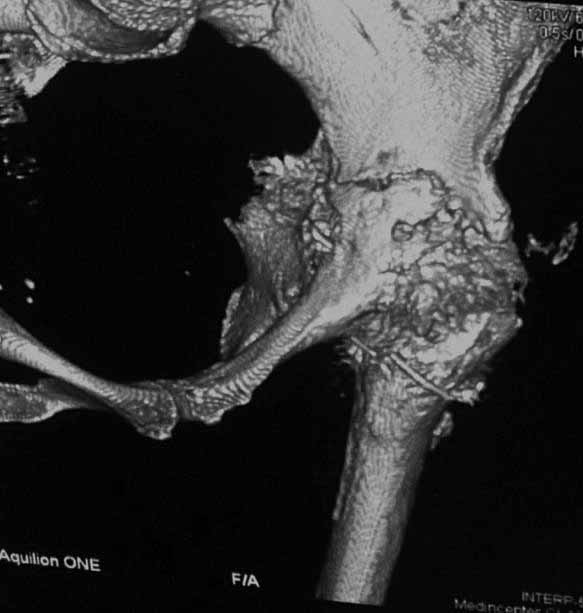

Уважаемые коллеги. Хотелось бы услышать мнения и советы по представляемому случаю. Пациентка 45 лет. Бесцементное эндопротезирование левого тазобедренного сустава 6 лет назад (впадина RM, Mathys, металл-металл, ножка Зульцеровская). За 10 лет до протезирования – коррегирующая остеотомия бедренной кости, которая не срослась в течение года до удаления пластины, а затем срослась в течение 3 месяцев иммобилизации в кокситной повязке. После протезирования получилось наблюдать пациентку почти постоянно, поскольку через 2 года синтезировал ей лодыжки на оперированной стороне, затем, через несколько месяцев удалил фиксаторы, а в 2009г. резецировал мениск на противоположной стороне. Боли все эти годы не беспокоили. Пациентка чуть выше среднего роста, вес тела нормальный. Физические нагрузки переносила хорошо. Работает на 7 этаже без лифта. Год назад экстирпация матки по поводу лейомиомы больших размеров. Несколько месяцев назад появились боли в области левого тазобедренного сустава. При рентгеновском и КТ исследованиях (июль с.г.) – нестабильность тазового компонента. От предложенной замены протеза пациентка на тот момент, слава богу, отказалась. Через какое то время боли в области левого тазобедренного сустава практически полностью прошли, а около 2 месяцев назад появилось ощущение патологической подвижности таза и боли в паху справа, которые через некоторое время уменьшились, а потом снова усилились после значительных физических нагрузок (много ходила по песку на пляже, носила тяжести). Ежедневно принимала диклофенак. На рентгенограммах – переломы правой лонной кости. Сейчас госпитализирована из-за болей в паху справа. Боли слева не беспокоят. На фоне снижения нагрузок в стационаре боли значимо уменьшились. Способна ходить без средств дополнительной опоры.В анализах крови чуть повышены трансаминазы и гамма-ГТ, моча без особенностей.

Вопросы: -правильно ли я расцениваю переломы как стрессовые на фоне неполноценного таза (pelvic insufficiency stress fractures)? -Можно ли так же расценить ситуацию на стороне протеза и, соответственно, не торопиться с ревизией, рассчитывая на вторичную стабилизацию? Уж больно не хочется менять ножку. -Если думать о ревизии, то когда? На представленных снимках тазобедренный сустав до и сразу после операции, затем 2 снимка 2009г., когда ничего не беспокоило, затем КТ 2-х месячной давности и вчерашние рентгенограммы обоих тазобедренных суставов.

При сравнении рентгенограмм можно увидеть насколько чашка переместилась от места своего первичного расположения. От опрокидывания ее удерживают конструкционные элементы "рожки". Без них ситуация, возможно, уже была бы катастрофической (чашка в тазу). Думаю надежды на вторичную интеграцию, могут быть обмануты и ревизии не избежать.

Если говорить о ревизии, то просто не будет и вероятность установки реконструктивного кольца достаточно высока, однако можно попробовать установить бесцементную высокопористую (для вторичной стабилизации врастанием) чашку с винтами , а по ходу операции решить вопрос о необходимости стабилизации таза пластиной.